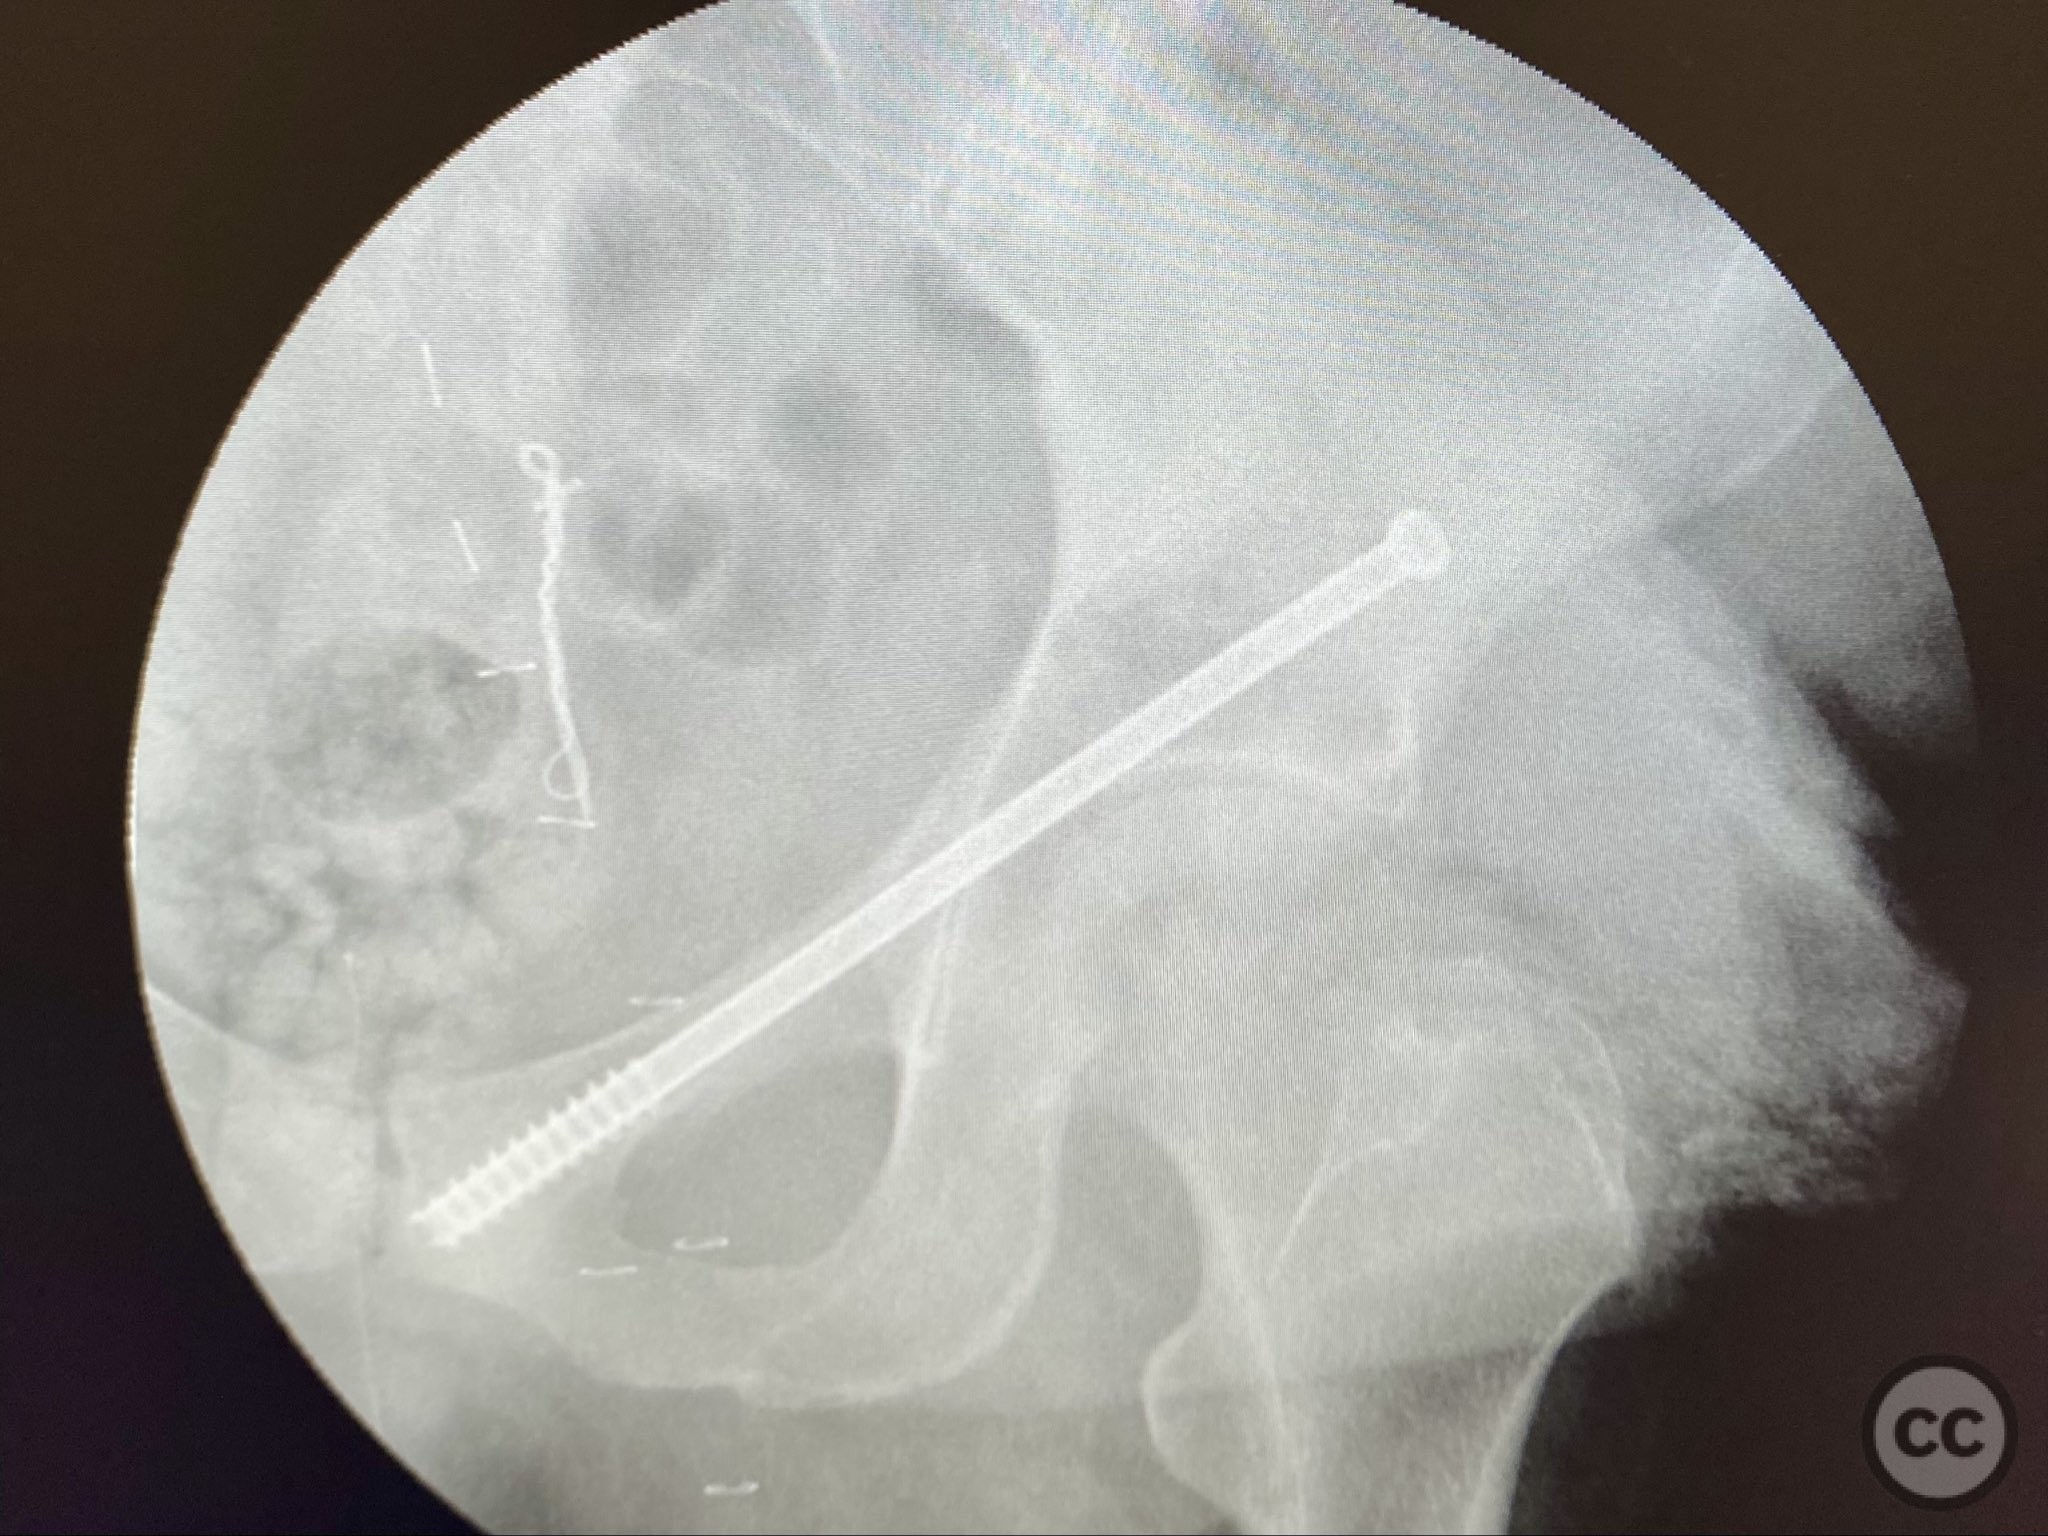

Operative remarks:

The transverse fracture was manipulated and temporarily stabilized using a reduction clamp applied across the fracture plane. Under biplanar fluoroscopic guidance, a cannulated cancellous lag screw was percutaneously inserted to achieve interfragmentary compression across the transverse component. The reduction clamp was then removed. Posterior wall fragments were anatomically reduced and stabilized with contoured buttress plates spanning both the posterior wall and providing additional stabilization to the transverse component. Postoperative CT confirmed satisfactory reduction and fixation of both acetabular columns and restoration of articular congruity.

Orthopaedic implants used:   Cannulated cancellous lag screw; contoured acetabular buttress plates